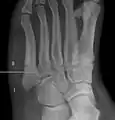

Jones fracture as seen on Xray

A person with a Jones fracture may not realize that a fracture has occurred. Diagnosis includes the palpation of an intact fibularis brevis tendon, and demonstration of local tenderness distal to the tuberosity of the fifth metatarsal, and localized over the shaft of the proximal metatarsal.

Diagnostic X-rays include anteroposterior, oblique, and lateral views and should be made with the foot in full flexion.

Pseudo-Jones fracture

Other proximal fifth metatarsal fractures exist, although they are not as problematic as a Jones fracture. If the fracture enters the intermetatarsal joint, it is a Jones fracture. If, however, it enters the tarsometatarsal joint, then it is likely an avulsion fracture caused by pull from the fibularis brevis tendon. An avulsion fracture at the base of the fifth metatarsal is sometimes called a "dancer's fracture" or a "pseudo Jones fracture", and usually responds readily to non-operative treatment.[18] The X-ray appearance of the developmental "apophysis" in this area may have some resemblance of a fracture, but is not a fracture; it is the secondary ossification center of the metatarsal bone. It is a normal finding that occurs at this site in adolescents.[19] If an injury to that area has occurred, the physician is often able to interpret certain radiographic clues to make the differentiation. An avulsion fracture at this location is typically extra-articular and oriented transversally as compared to the longitudinal orientation of an unfused apophysis.[19]